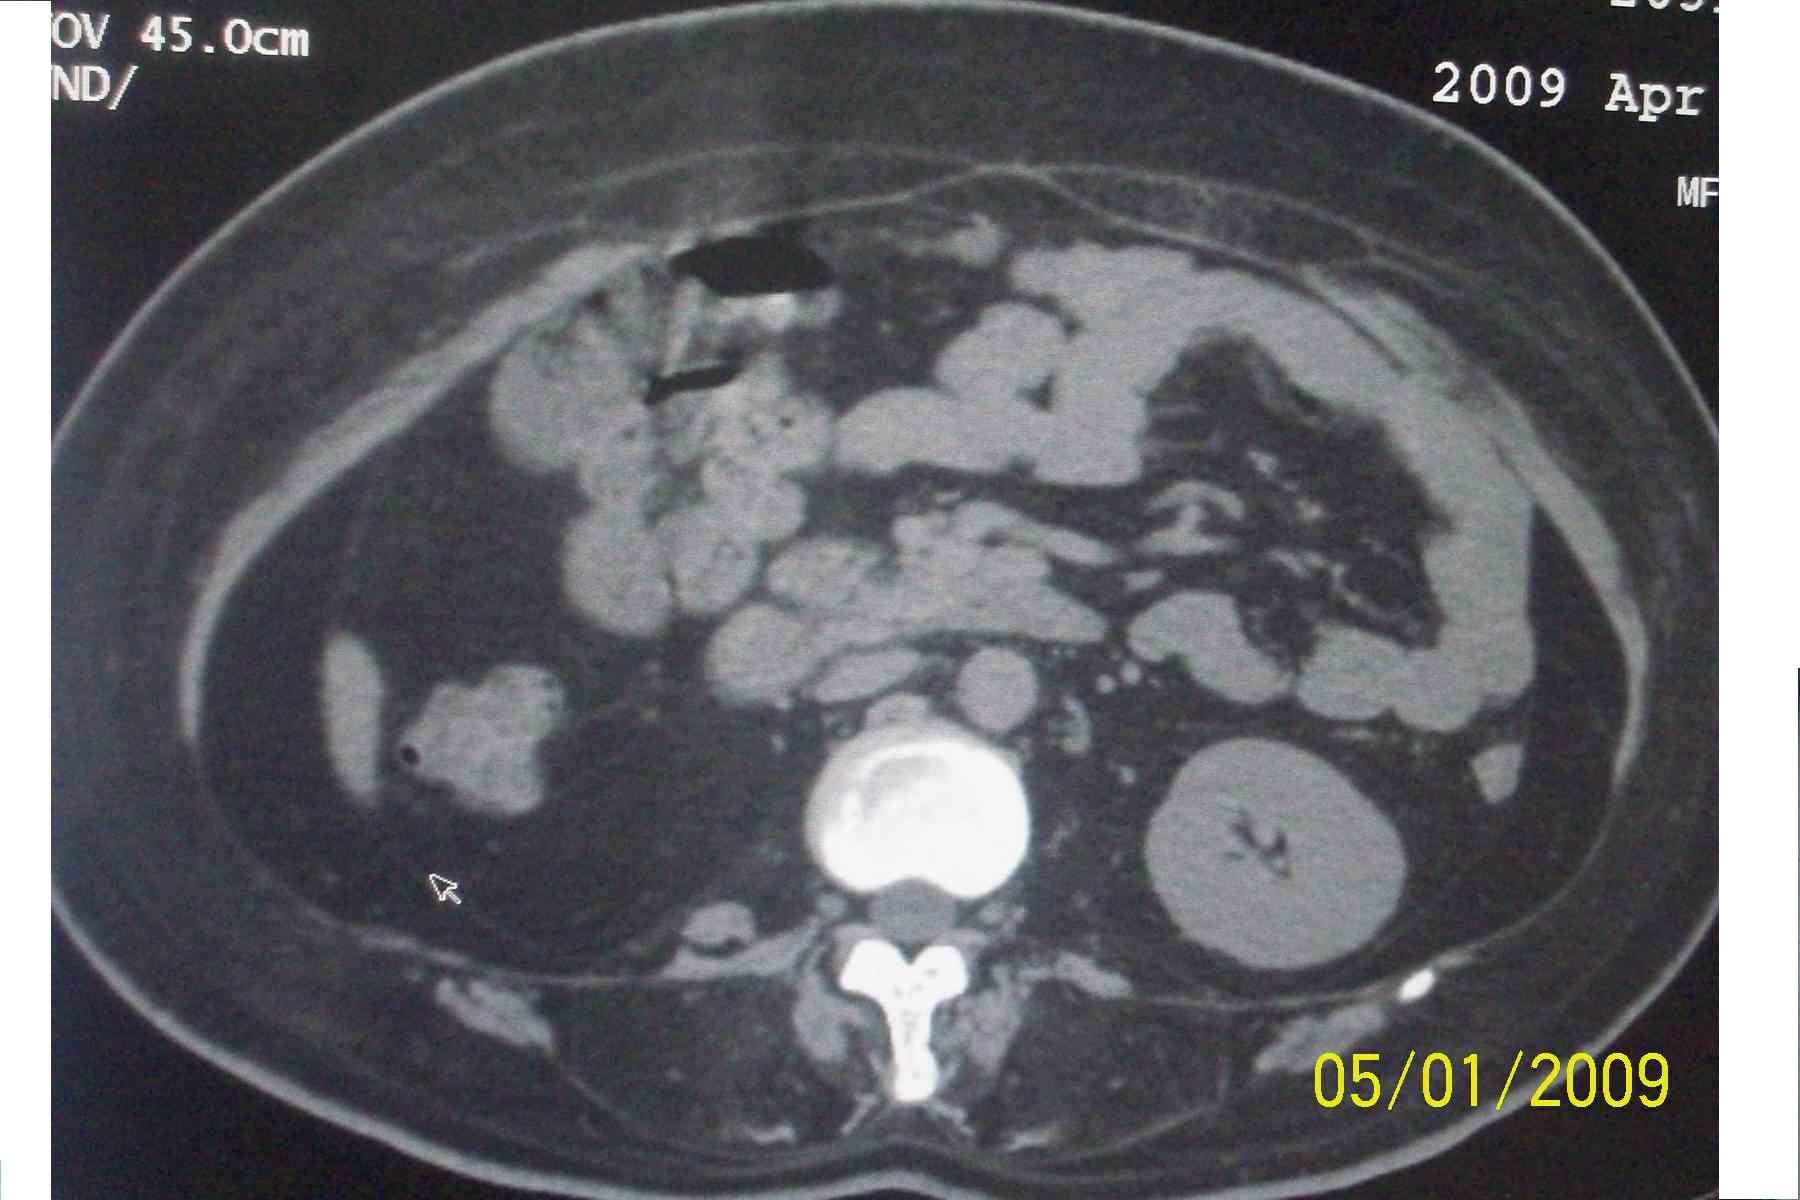

以下是引用杀毒软件在2009-5-1 17:43:00的发言:[br]良性对称性脂肪增多症

以下是引用ncy888888在2009-5-1 17:39:00的发言:[br]肾怎么弄丢了一个。